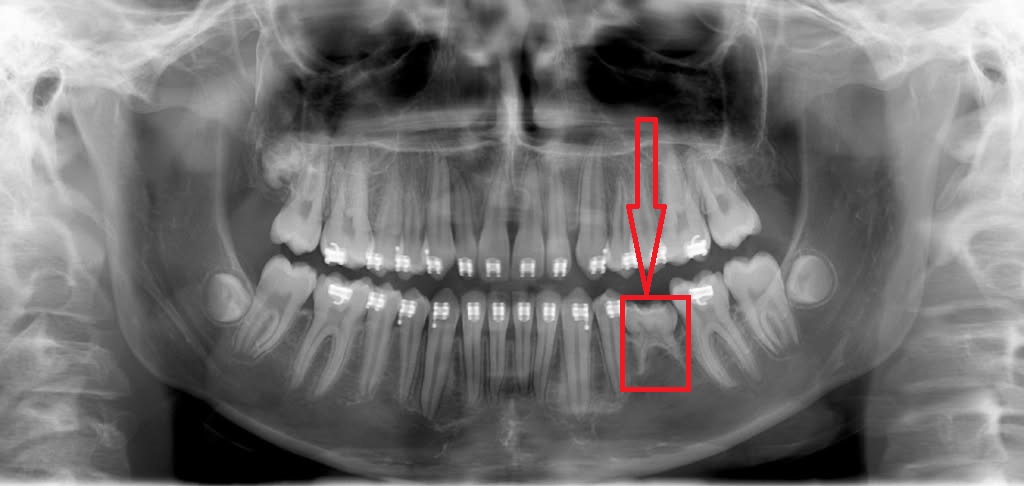

Trong chỉnh nha, sự di chuyển của răng thực chất là quá trình tái cấu trúc xương ổ răng dựa trên cơ chế tiêu xương ở phía áp lực và bồi xương ở phía sức căng. Đối với nhóm khách hàng có xương quá mỏng hoặc đang gặp tình trạng tiêu xương lan tỏa, mật độ xương không đủ để đáp ứng chu trình này.

Khi bác sĩ tác động lực siết từ mắc cài, quá trình tiêu xương diễn ra nhanh hơn bồi xương. Hậu quả là không có xương lưu giữ, tụt lợi hoặc chân răng bị đẩy ra khỏi bản xương. Do đó, các bác sĩ bắt buộc phải chỉ định khách hàng chụp phim x-quang để khảo sát tình trạng xương.

Khách hàng đã bị tiêu xương, mất xương lan tỏa có thể không đủ điều kiện niềng răng

Những người không nên niềng răng do xương mỏng/tiêu xương thường chiếm từ 1% đến 3% và bác sĩ buộc lòng phải từ chối chỉnh nha để bảo tồn răng thật. Giải pháp khác là phục hình thẩm mỹ răng sứ để điều chỉnh trục răng trong giới hạn cho phép. Trong trường hợp khách hàng đã bị mất răng trên nền xương yếu, việc cấy ghép Implant kết hợp ghép xương sẽ là phương án bền vững hơn để khôi phục chức năng ăn nhai và thẩm mỹ mà không gây áp lực quá tải lên hệ thống xương hàm vốn đã mỏng manh.